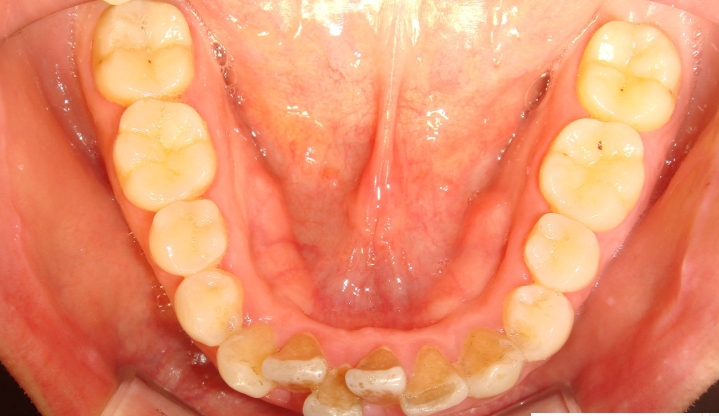

어떻게 변했는지 사진 보세요.

잘 되었지요?

발치하지 않고도 토끼이나 돌출된 앞니는 이렇게 변할 수 있습니다.

위에서 보았을 때 튀어나온 앞니가 들어간 사실을 확인할 수 있고요

아까 위에서 봤던 틀어진 두 개의 앞니가

지금 보시면 가지런히 펴진 것이 보이시죠

빗발치로 이렇게 예쁘게 교정될 수가 있습니다.